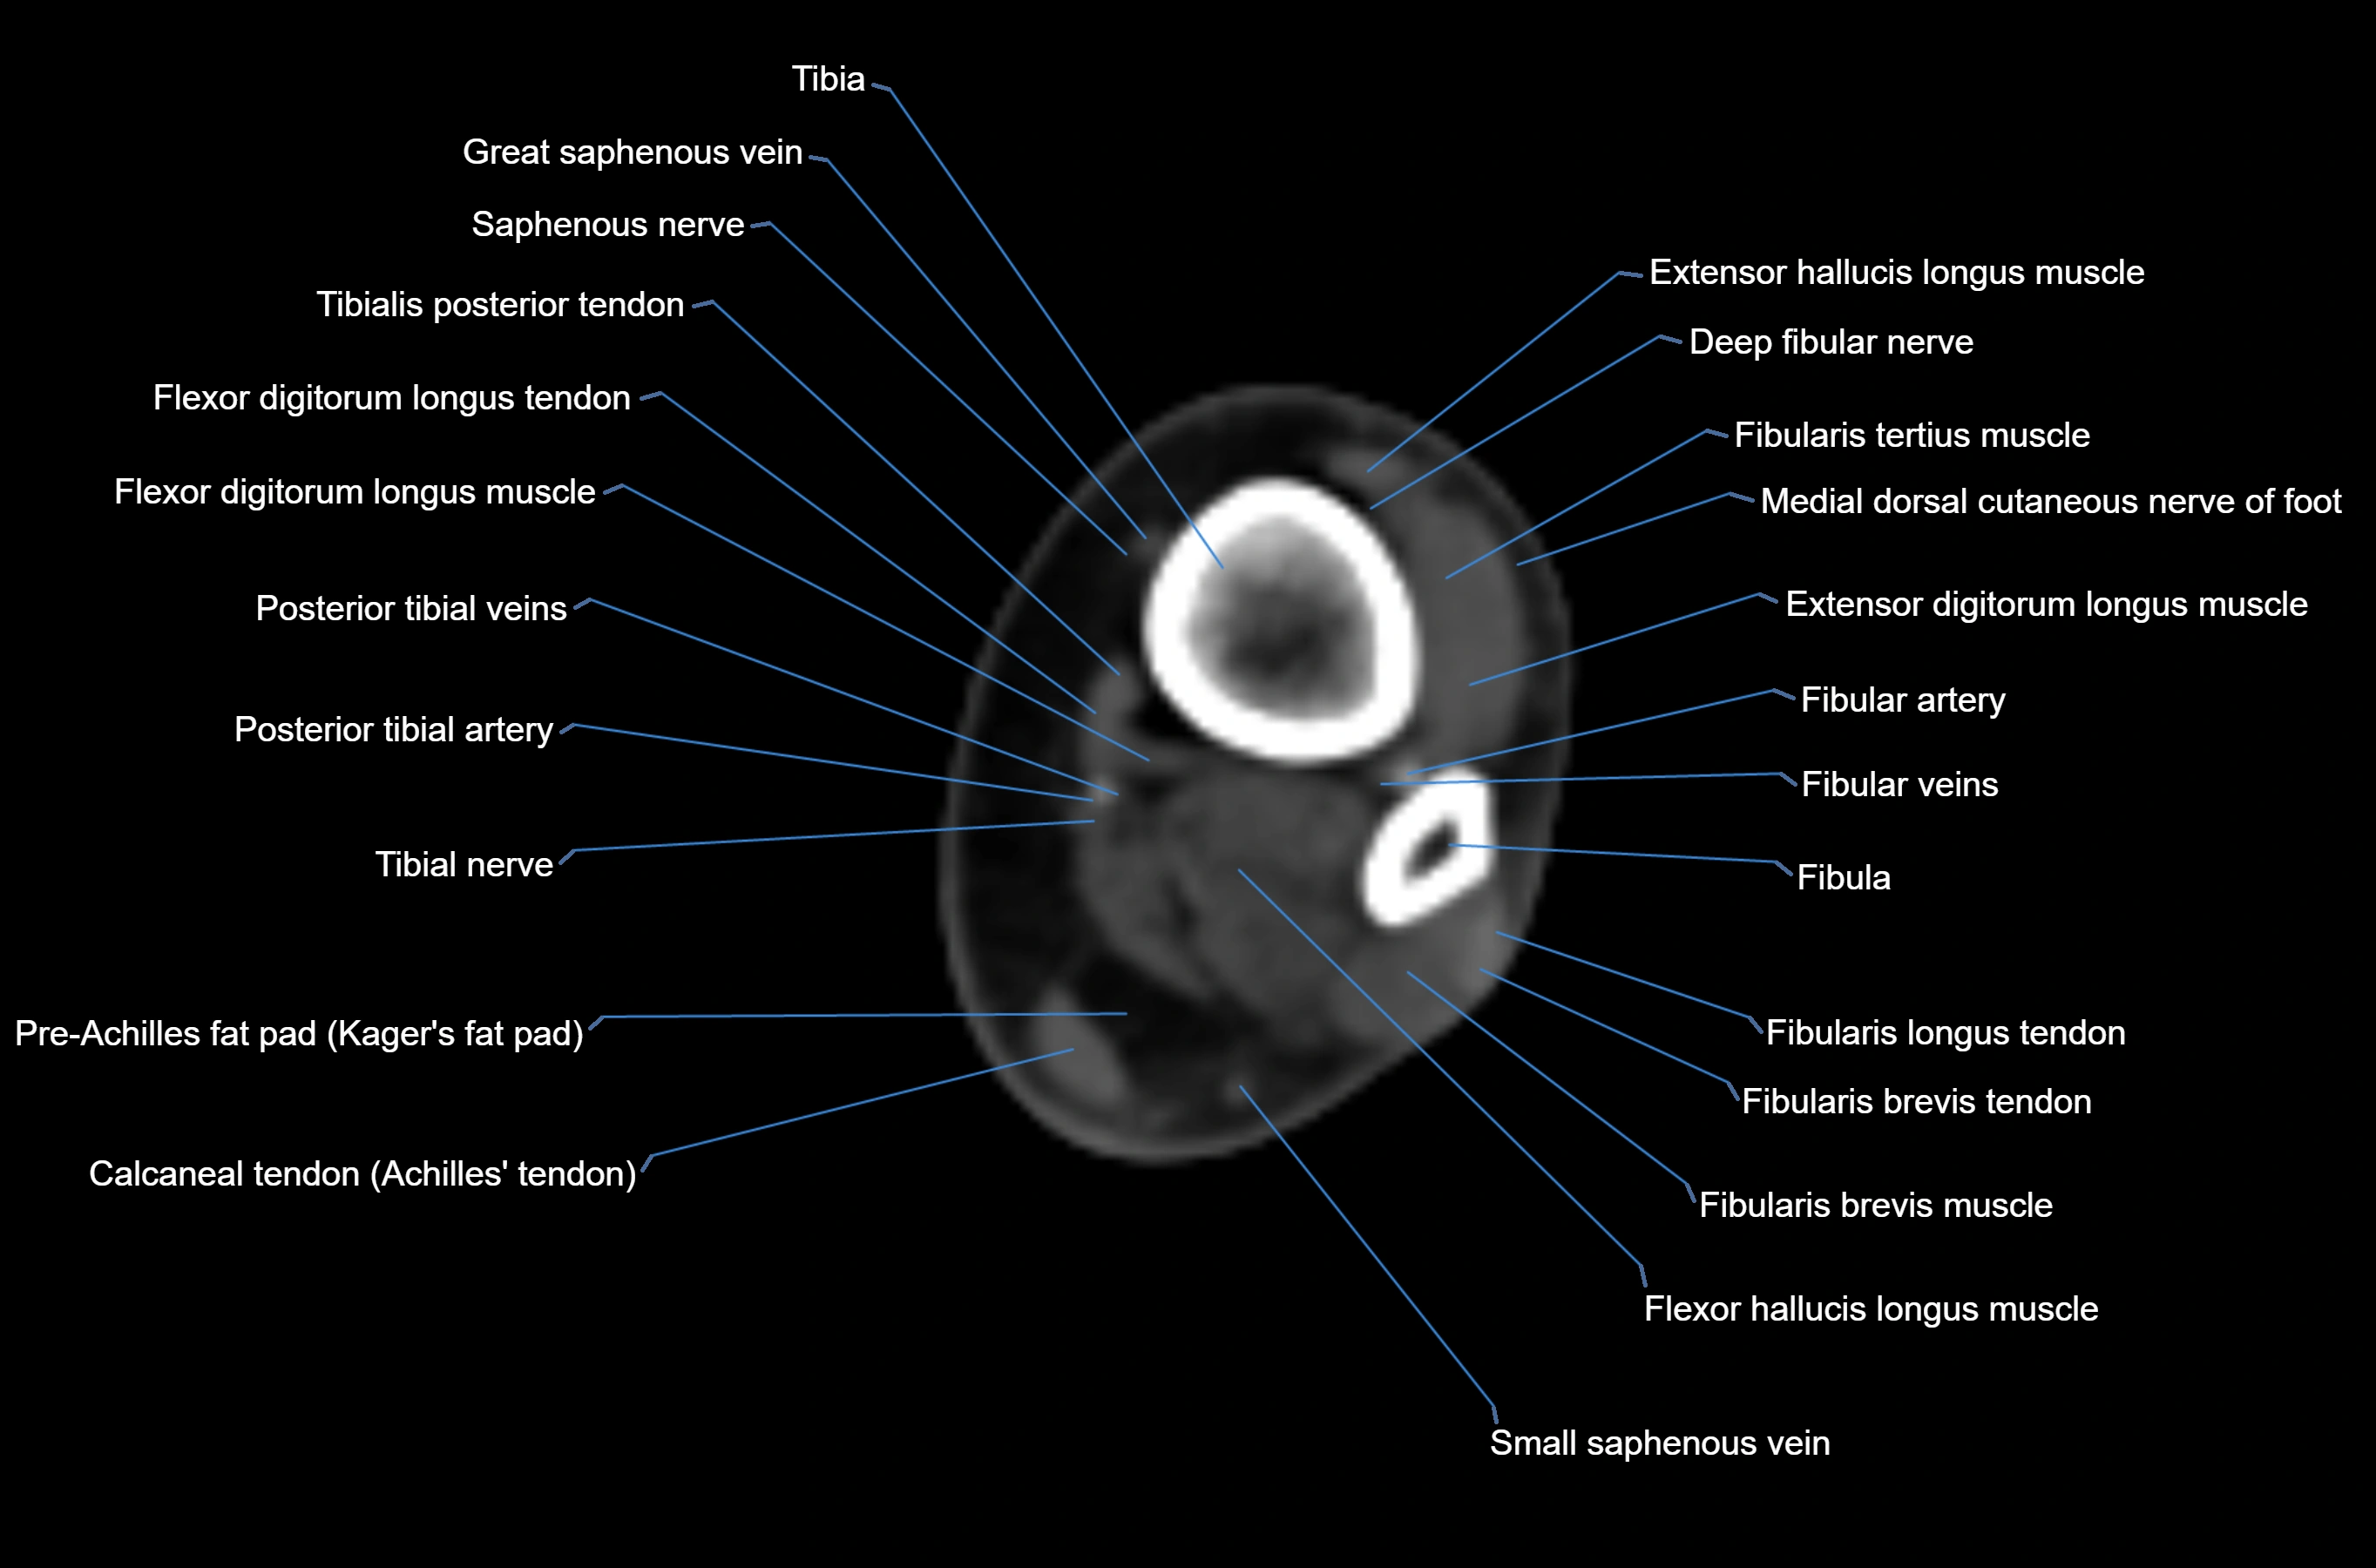

CT image